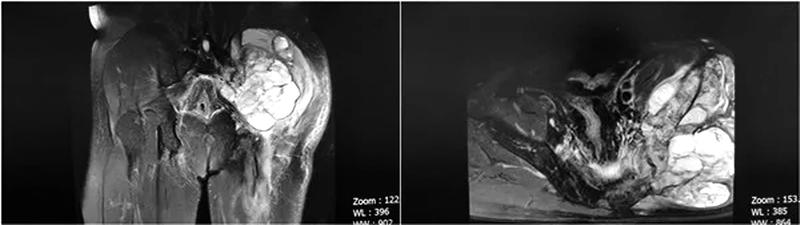

患者是一名51岁的男性,八个月前不慎左臀部受伤,局部肿痛明显,以外伤于当地医院就诊后予对症治疗,但无明显改善并且症状加重,做臀部CT及磁共振检查后,显示骨盆巨大软组织肿瘤,合并髂骨病理性骨折并向盆腔侵袭。患者于省内多家三甲医院就诊,行肿块穿刺活检,病理结果提示“高级别肉瘤,伴肌源性分化”。患者辗转来到西安交大二附院骨三科,张纯教授团队复查CT及磁共振发现肿瘤包绕坐骨神经并与盆腔大血管关系密切,术中极易出现大出血及神经损伤导致严重并发症。

全科对患者病情进行术前讨论并做好充分准备,术前行骨盆3D打印。院内多学科MDT会诊,肿瘤科、普外科分别给予专业建议,并在介入科行血管栓塞治疗。术中可见瘤体约25*15*10cm大小,侵蚀左侧髂骨约10*7cm,并向盆腔内呈梭形侵蚀约8*6cm,于坐骨大孔处包绕坐骨神经,结合术前3D打印,手术历时6小时,出血600ml,完整行肿瘤囊外切除,一并切除髂骨病灶,并予术中重建,术中全程电生理监测显示神经损伤未加重。肉瘤是一种间叶源性恶性肿瘤,其来源多种多样,包括脂肪组织、血管和淋巴管、平滑肌、横纹肌、纤维组织、骨及软骨组织等。